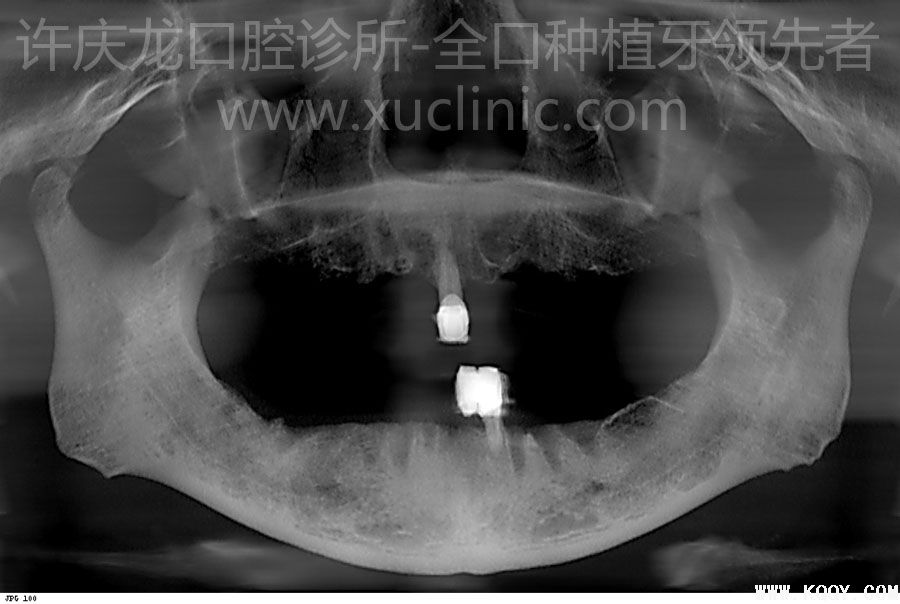

患者,女,2012年6月初诊,时年53岁。全身状况良好。因牙周病拔出大部分牙齿一个月。上下颌后牙区骨量不足,骨质不佳(图1、2、3、4、5、6)。前牙区骨质骨量佳。(图7、8、9、10、11、12、13、14)

| 图2.术前全景片 |

附X光片(图2,47,48,49,50,51,52,53,54)

![]() |

| 图47.术后当日 |